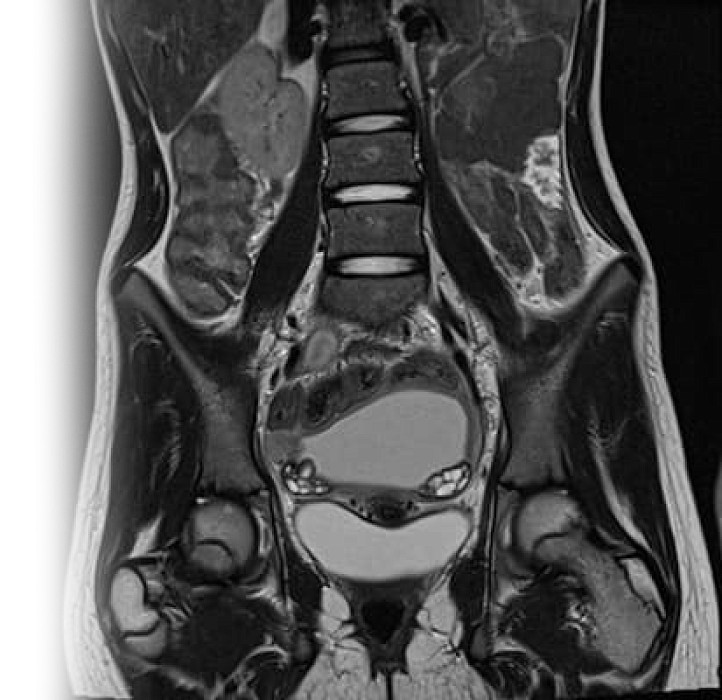

Магнитно-резонансная томография костей таза – важный метод исследования, который позволяет визуализировать проксимальные отделы бедренных костей, вертлужных впадин, лонных костей, мышц, связок, сухожилий, крестцово-подвздошных сочленений.